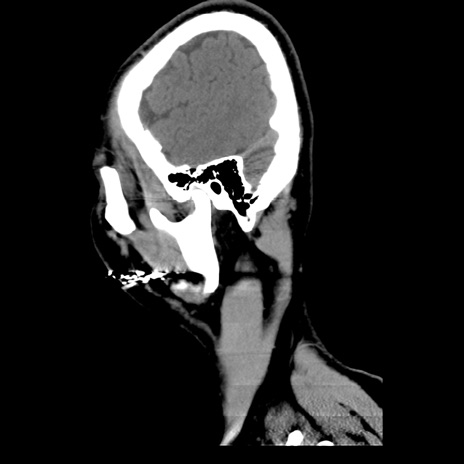

【頭部】TIPS症例12 CT

【症例】40歳代男性

松果体にあるものはなに?